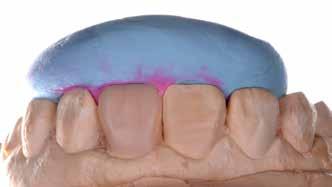

A fogászati kezelések során manapság már nem kizárólag az esztétikai megjelenés helyreállítására törekszünk. Sokszor a kedvezőtlen esztétikai megjelenés hátterében álló okok következményes módon a fogazat funkcionális működését is károsítják, így a kezelések során ezeknek a helyreállításával is foglalkoznunk kell. A különböző funkcionális és esztétikai diszkrepanciák kezelésére számtalan módszer létezik, ám ezen fogászati beavatkozások mindegyikében közös, hogy a kivitelezésük során nagyon szoros együttműködésre van szükség a kezelést végző fogorvos és a munkáját segítő fogtechnikus között. Az alábbi esetbemutatás során egy fiatal hölgypáciens fogazatának héjak alkalmazásával történő esztétikai és funkcionális rehabilitációját szeretnénk ismertetni.

A 19 éves hölgypáciens azzal a kéréssel jelentkezett a rendelőnkbe, hogy szebb fogakat szeretne. Az első konzultáció alkalmával megkérdeztük, hogy mi zavarja leginkább a fogazatának jelenlegi megjelenésében, valamint azt is megbeszéltük vele, hogy milyen végeredmény elérése esetén lenne maradéktalanul elégedett. Ebben az esetben a kezelési célokat az alábbiakban határoztuk meg:

A páciens fogazata esztétikai megjelenésének és funkcionális működésének a lehető legtöbb, saját foganyag megtartása mellett történő helyreállítása (1. és 3. ábra).

A kezelés megtervezése során kifejezett jelentősége van annak, hogy jó kommunikáció legyen a páciens, a fogorvos és a fogtechnikus között. A páciens leendő fogazatának természetes megjelenését a kezelésben részt vevő team szakmai felkészültsége, gyakorlati tapasztalata és a kezelés sikerességének irányába történő elkötelezettsége biztosítja. A beavatkozások megkezdése előtt megtörtént a páciens anamnézisének a felvétele, valamint a klinikai kivizsgálását is elvégeztük. Ezt követően lenyomatokat készítettünk a kiindulási állapotról, majd a kiindulási helyzetet extra- és intraorális fotók segítségével is rögzítettük (13. a-c. ábra).

A kezeléstervezés egyik legfontosabb lépése a mock-up elkészítése. A mock-up alapjául szolgáló wax-up-ot (felviaszolás) is ugyanolyan részletességgel kell a fogtechnikusnak elkészíteni, mintha azok már a végleges fogpótlások alapjául szolgáló mintázatok lennének. A mock-upnak nagyon pontosan kell illeszkednie, valamint a tervezett fogpótlás meg-

jelenését is rendkívül élethűen kell reprezentálnia. Ahhoz, hogy a páciens mock-uppal kapcsolatos első benyomásai kedvezőek legyenek, a mock-up színének a páciens „szemfehérjének” színével meg kell egyeznie. A kezelési cél páciens által történő elfogadása és a tervezett eredménnyel kapcsolatos „wow-effektus” kialakulása nagyban függ a páciensben az első megtekintés során kialakult első benyomásoktól.

Az eddigi tapasztalataink szerint a páciensek jelentős többsége egyértelműen kifejezi az elégedettségét, ha a mock-up megfelel az eredeti elképzeléseiknek. A bemutatásra kerülő esetben is ez történt. A tervezett végeredmény megtekintését követően a páciens azonnal kérte az általunk javasolt kezelési tervben ismertetett beavatkozások elvégzését. A héjak alapanyagául az Ivoclar Vivadent által gyártott A1-es színű Telio CS kerámiát javasoltuk. Az anyagválasztás hátterében az állt, hogy ez az anyag nagy keménységgel rendelkezik, valamint az, hogy a felszínét nagy simaságúra lehet polírozni. A páciens rendkívül fiatal életkora is azt a terápiás koncepciót erősítette, hogy a kezelés során lehetőség szerint kizárólag non-invazív beavatkozásokat alkalmazzunk.

A tényleges protetikai ellátás megkezdése előtt a páciens mosolygás közben látható fogait otthoni fogfehérítés keretei között a kérésének megfelelő A1-es fogszín eléréséig fehérítettük. A fehérítés során a későbbiekben héjakkal ellátásra kerülő fogak színén nem változtattunk. A fogak előkészítése részeként csupán a két felső nagymetsző (1.1,2.1) incizális élét kellett kismértékben redukálni. A többi felső front fog (1.3,1.2,2.2,2.3) nem került preparálásra.